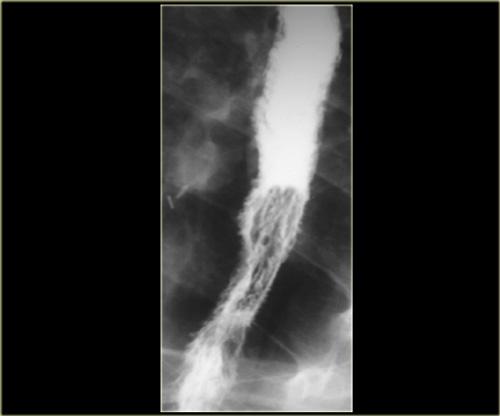

Bên trái: co bóp bậc ba ở lần nuốt đầu tiên (trái).

Co bóp nguyên phát bình thường ở lần nuốt tiếp theo (phải).

Các co bóp bậc ba này là những co bóp không có tính đẩy, thoáng qua và không liên tục, không cố định về vị trí và không kèm theo triệu chứng, thường gặp ở bệnh nhân cao tuổi.

A. Co bóp bậc ba không có tính đẩy ban đầu B. Ba hình ảnh trong quá trình thăm khám cho thấy các ổ đọng thuốc giống túi thừa C. Hình ảnh chụp muộn hơn trong quá trình thăm khám cho thấy các co bóp bậc ba đã biến mất

Đôi khi các co bóp bậc ba thoáng qua có thể giả dạng túi thừa.

Bên trái là hình ảnh của một bệnh nhân có co bóp bậc ba, trong quá trình thăm khám trông giống như túi thừa.